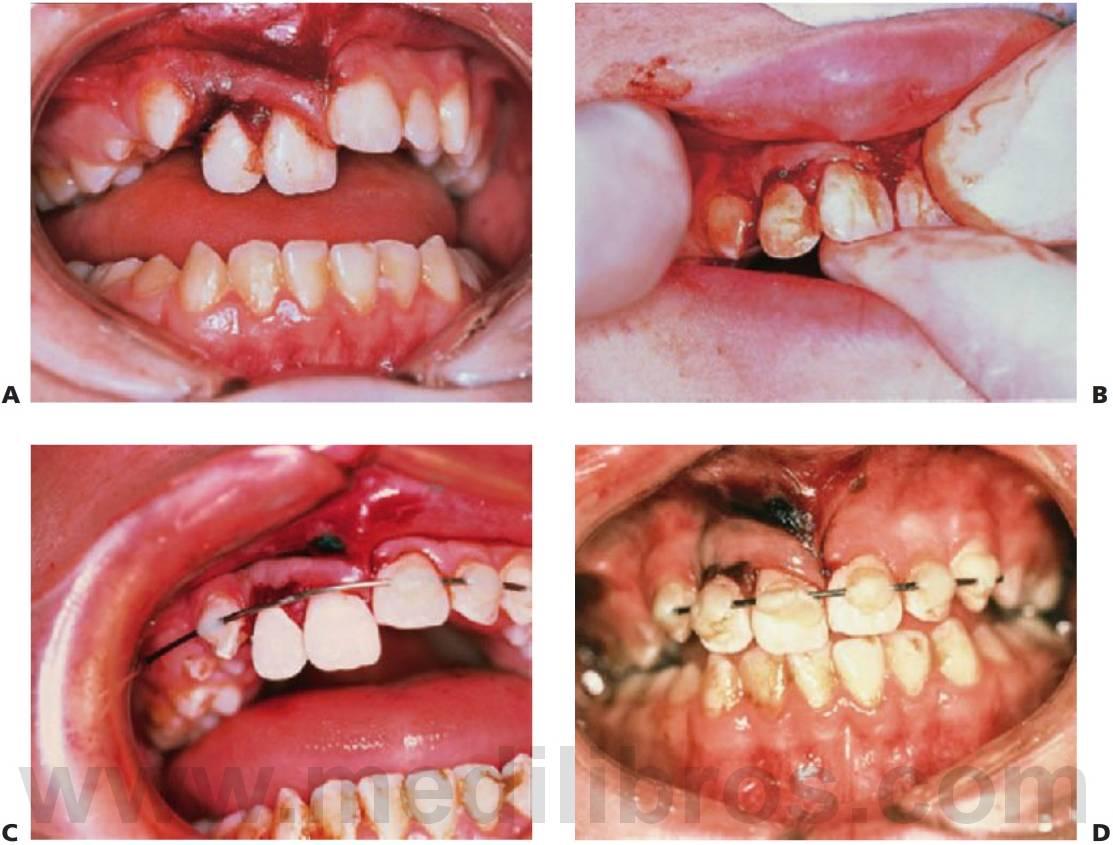

El tratamiento de los traumatismos maxilofaciales en un niño es complicado debido a la presencia de dentición que no ha erupcionado, a la ansiedad, a las consideraciones derivadas del crecimiento y, por último, a la asociación habitual de traumatismos craneales cerrados que pueden retrasar el tratamiento completo. El uso de fijaciones internas como miniplacas y tornillos debe hacerse con cautela para no perjudicar el desarrollo de los gérmenes dentarios y la fijación intermaxilar; con la posible combinación con alambres transóseos, es bien tolerada por los niños. Se pueden utilizar las barras de arco como fijación dental, pero las férulas de plata sobrepuestas son las que se utilizan con más frecuencia de una forma eficaz. Con una adecuada reducción, fijación e inmovilización, así como un tratamiento antibiótico profiláctico y un estricto cuidado oral, las fracturas se unen en 3 semanas. No existe apenas constancia de la no unión o la unión fibrosa.

- Reducción y fijación con barras de arco y fijación intermaxilar elástica o con alambres.

- Las férulas pueden cementarse con ionómero de vidrio o con cemento de cobre negro o retenido con alambres circunmandibulares.

- Fertilización flexible con resina composite y alambre (fig. 7.24C, D) o aparatología ortodóncica durante 2 semanas para la luxación extrusiva y durante 4 semanas para la luxación lateral debido a la fractura de hueso alveolar concomitante.